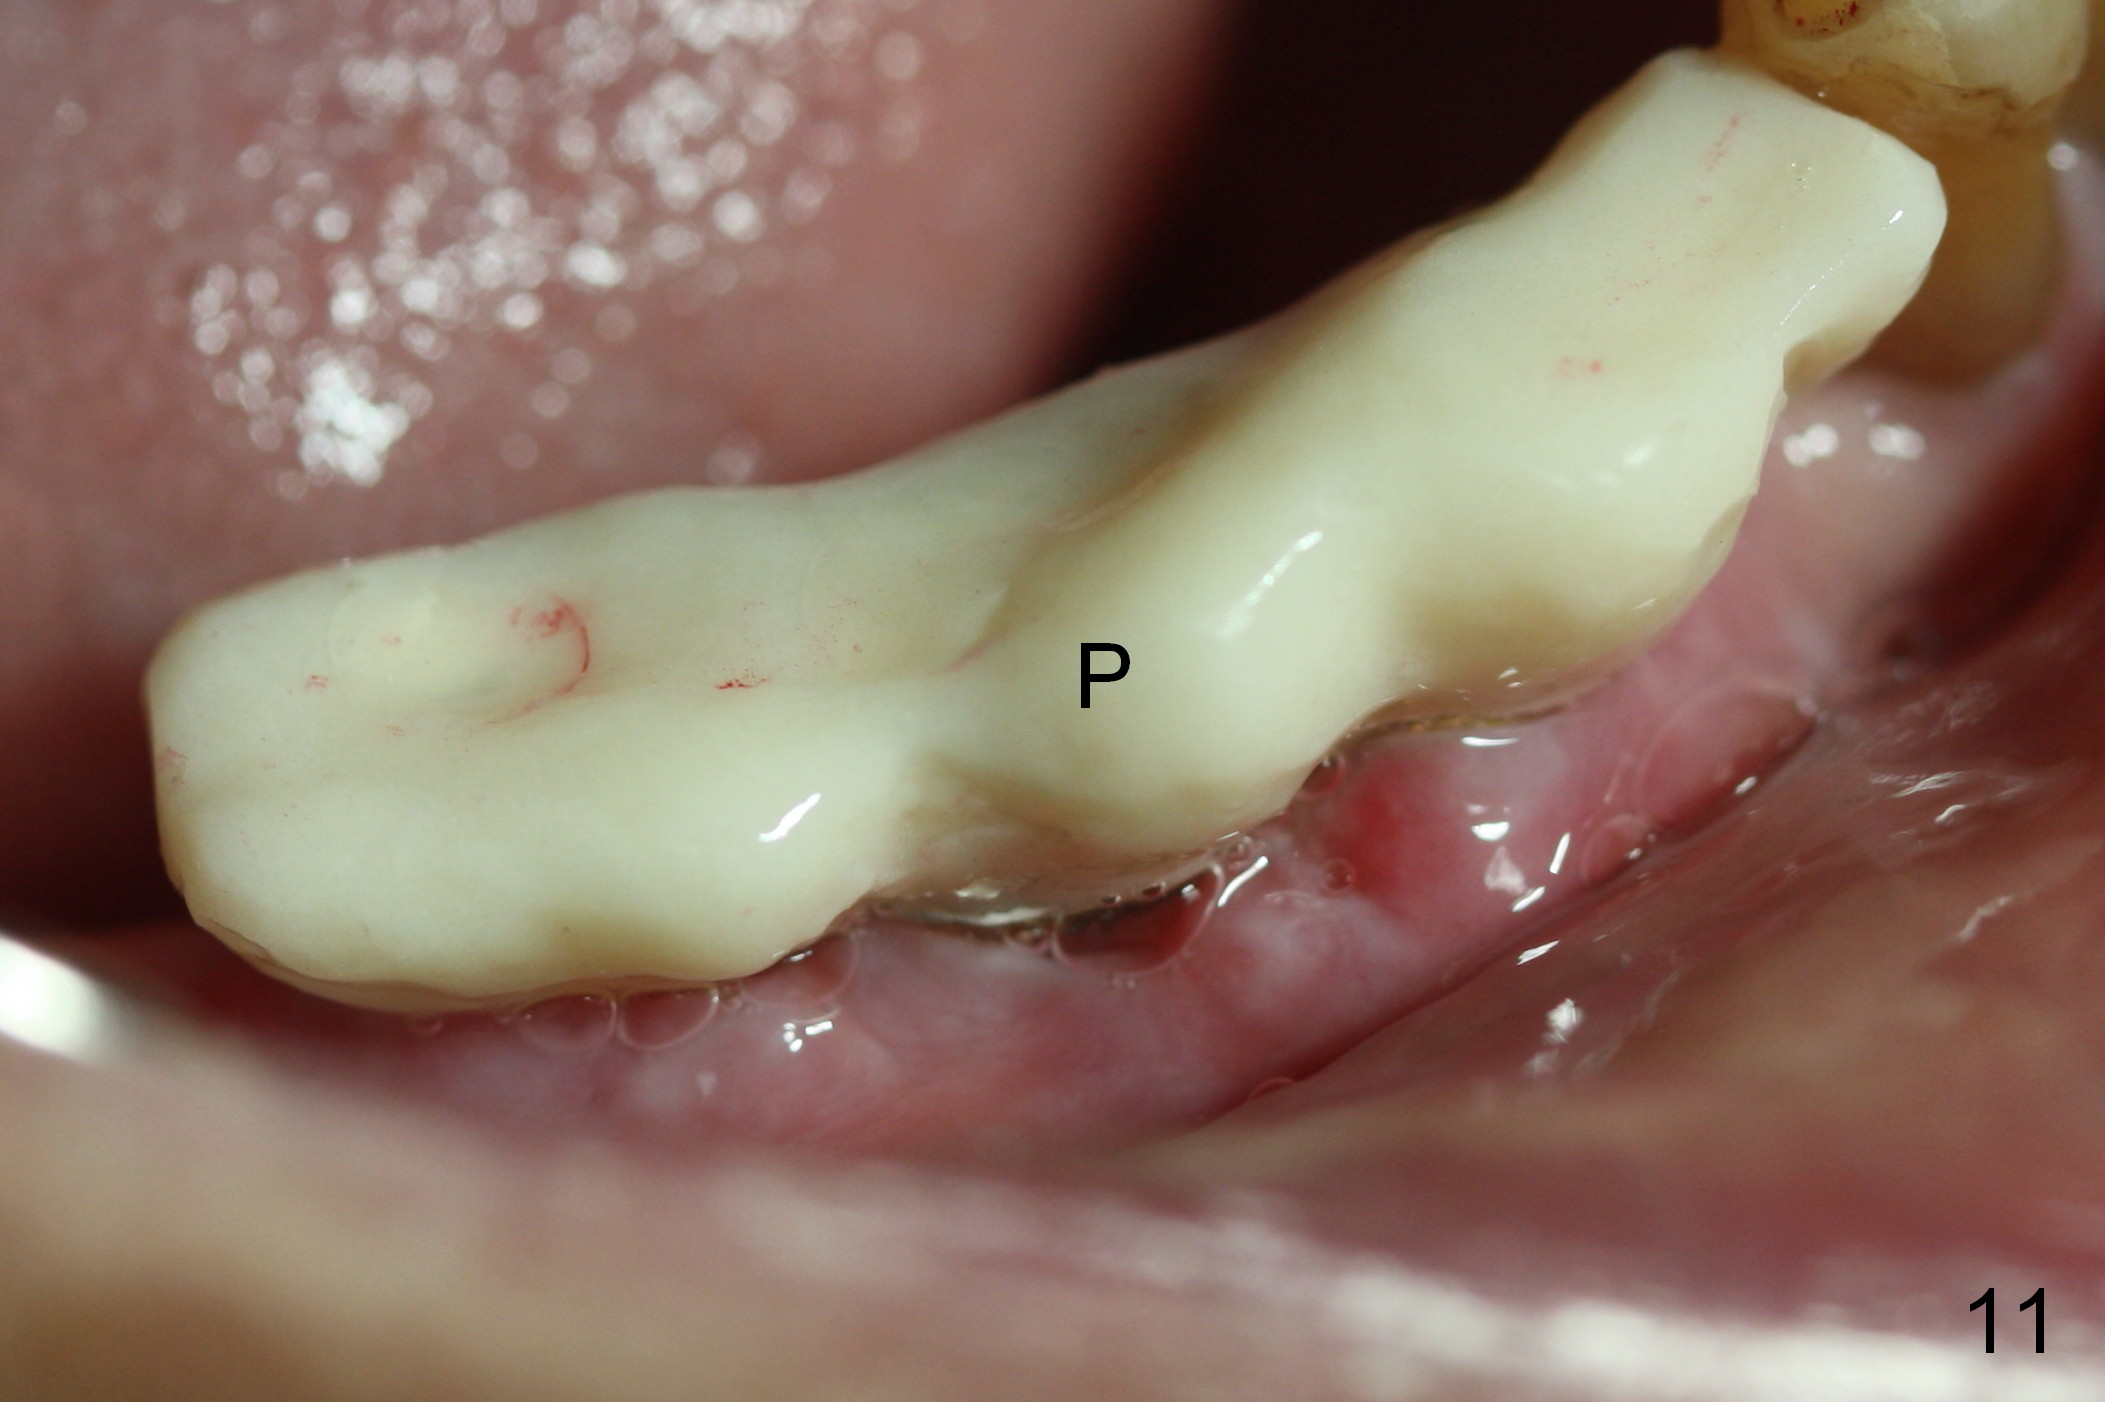

Eight days postop, the most anterior portion of the perio dressing is dislodged; the rest is stable (Fig.9). Since the patient has difficulty in coming to office, the perio dressing is removed. While the buccal gap of #27 has closed apparently (Fig.10 ^), that of #28 not (*). To prevent irritation from the abutments, a splinted provisional is fabricated (Fig.11 P). Perio dressing should have been re-applied buccal to the gap at the site of #28 or preferably the original perio dressing should have not been removed prematurely.